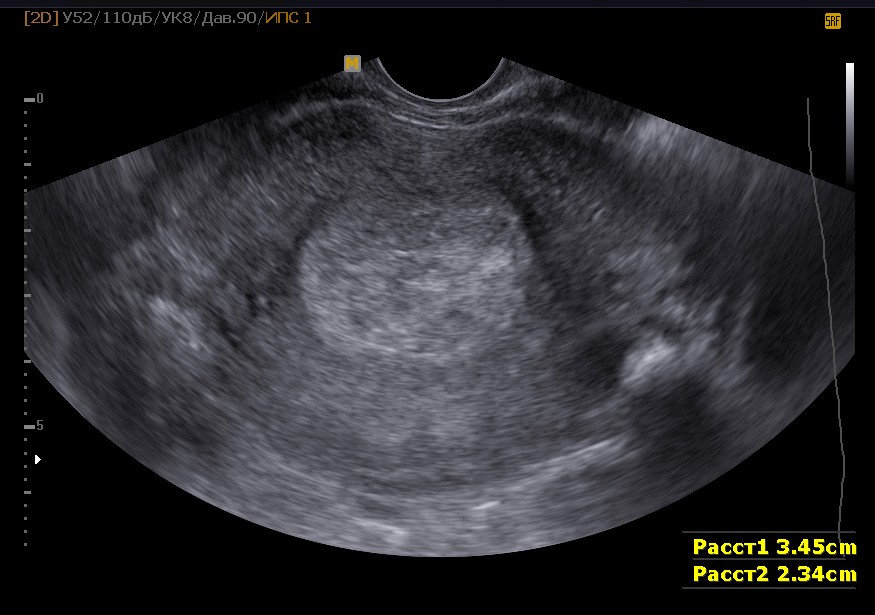

Как же осуществляется данное исследование? В зависимости от того, имеется ли беременность или нет, оно может осуществляться немного по-разному. В частности, речь идет именно о методе исследования. При отсутствии беременности почти всегда используется трансвагинальный метод, так как с его помощью удается достичь максимально близкого расположения датчика к исследуемой области. В результате информативность такого исследования гораздо выше, чем трансабдоминального (в большинстве случаев), при котором картина менее четкая.

В случае отсутствия беременности, как уже упоминалось ранее, назначается трансвагинальное ультразвуковое исследование. Специальная подготовка для этого метода не требуется. В отличие от трансабдоминального исследования, которое необходимо проводить на полном мочевом пузыре, трансвагинальный метод не имеет таких ограничений. Все, что нужно от пациентки – это принести презерватив для использования на датчике в целях гигиены. Также в некоторых медицинских учреждениях могут отсутствовать одноразовые пеленки, поэтому рекомендуется взять с собой полотенце – об этом врач сообщит заранее при назначении процедуры.

Во время исследования пациентка снимает верхнюю одежду и располагается в гинекологическом кресле, на которое заранее укладывается одноразовая простыня, пеленка или полотенце. В влагалище вводится трансвагинальный датчик УЗИ, предварительно помещенный в презерватив и обработанный специальным гелем. Процедура занимает около 10-15 минут, в ходе которой врач визуализирует как шейку матки, так и ее тело. Этот метод позволяет не только оценить биометрические параметры, но и выявить возможные патологии, такие как новообразования или отклонения в состоянии эндометрия и т. д.

Значение такого исследования на разных сроках беременности очень велико. Проводиться оно может трансвагинальным или трансабдоминальным методом. На ранних сроках, обычно, применяется первый способ, как более информативный. На более поздних – второй способ также становится достаточно информативным. Но такое исследование обязательно необходимо выполнять строго на полный мочевой пузырь, так как только таким образом достигается максимальная визуализация исследуемого органа.

Биометрия шейки матки при беременности необходима потому, что позволяет сделать предварительные выводы о характере вынашивания и о возможных сложностях, которые могут угрожать ребенку. На сроке до 12 недель такое исследование позволяет наблюдать за развитием беременности, помогает диагностировать наличие новообразований, инфекций, а также позволяет установить, почему в предыдущие сроки беременность самопроизвольно прерывалась.

Расшифровка

Биометрия шейки матки во время беременности помогает ответить на несколько ключевых вопросов:

- Достаточно ли размеры шейки матки для того, чтобы удерживать плод на протяжении всего срока вынашивания;

- Развивается ли беременность нормально, поскольку длина и другие характеристики шейки матки должны изменяться по мере увеличения срока беременности;

- Существует ли риск выкидыша, который может возникнуть при укорочении шейки матки до менее чем 3 см?

Какие же нормальные показатели биометрии матки при беременности? В первом триместре длина шейки не должна превышать 3 см. На 12-й неделе она увеличивается до 3,5-4,5 см. После 32-й недели наблюдается постепенное укорочение шейки, что свидетельствует о подготовке организма к родам. Если беременность повторная, длина шейки может быть немного меньше указанных значений, и это не будет считаться отклонением.